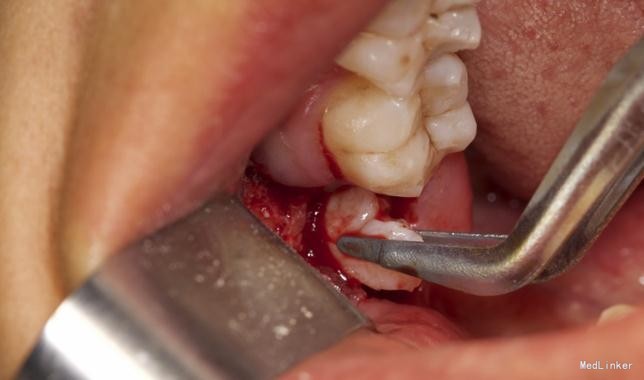

患者,男,25岁,要求拔除左下颌水平阻生牙齿,平素体质一般,无药物、食物过敏史,无高血压、心脏病等系统病史

拔除术

挺好的病例,图片也很清晰,牙齿分的很好,我之前拔过类似的牙,牙齿分开后近中撬不动,最后又T型分开近中后才弄出来

水平阻生拔除的难度还是很大的,图片看着创伤不是很大,能不能把您拔牙时的阻力分析和该牙具体的拔牙步骤给我们说一下呢?谢谢~